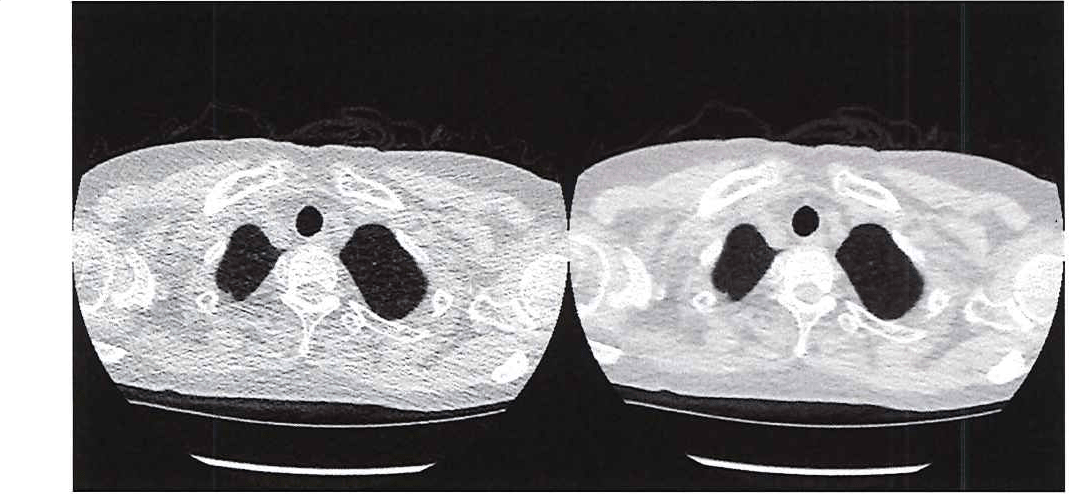

Medical researchers want to limit radiation exposure while providing physicians with the image clarity they need. One promising approach is the use of ultra-low-dose CT, which has an effective average dose of about 0.13 mSv for a chest image. [1] The principal drawback of ultra-low-dose CT scans is their relatively low resolution and high level of noise, which can make it difficult for physicians to see organs, fat, and interstitial tissue (Figure 1).

Figure 1. Comparing the image quality of ultra-low-dose CT with a traditional CT.

Figure 1. Comparing the image quality of ultra-low-dose CT (left) with a traditional CT (right).